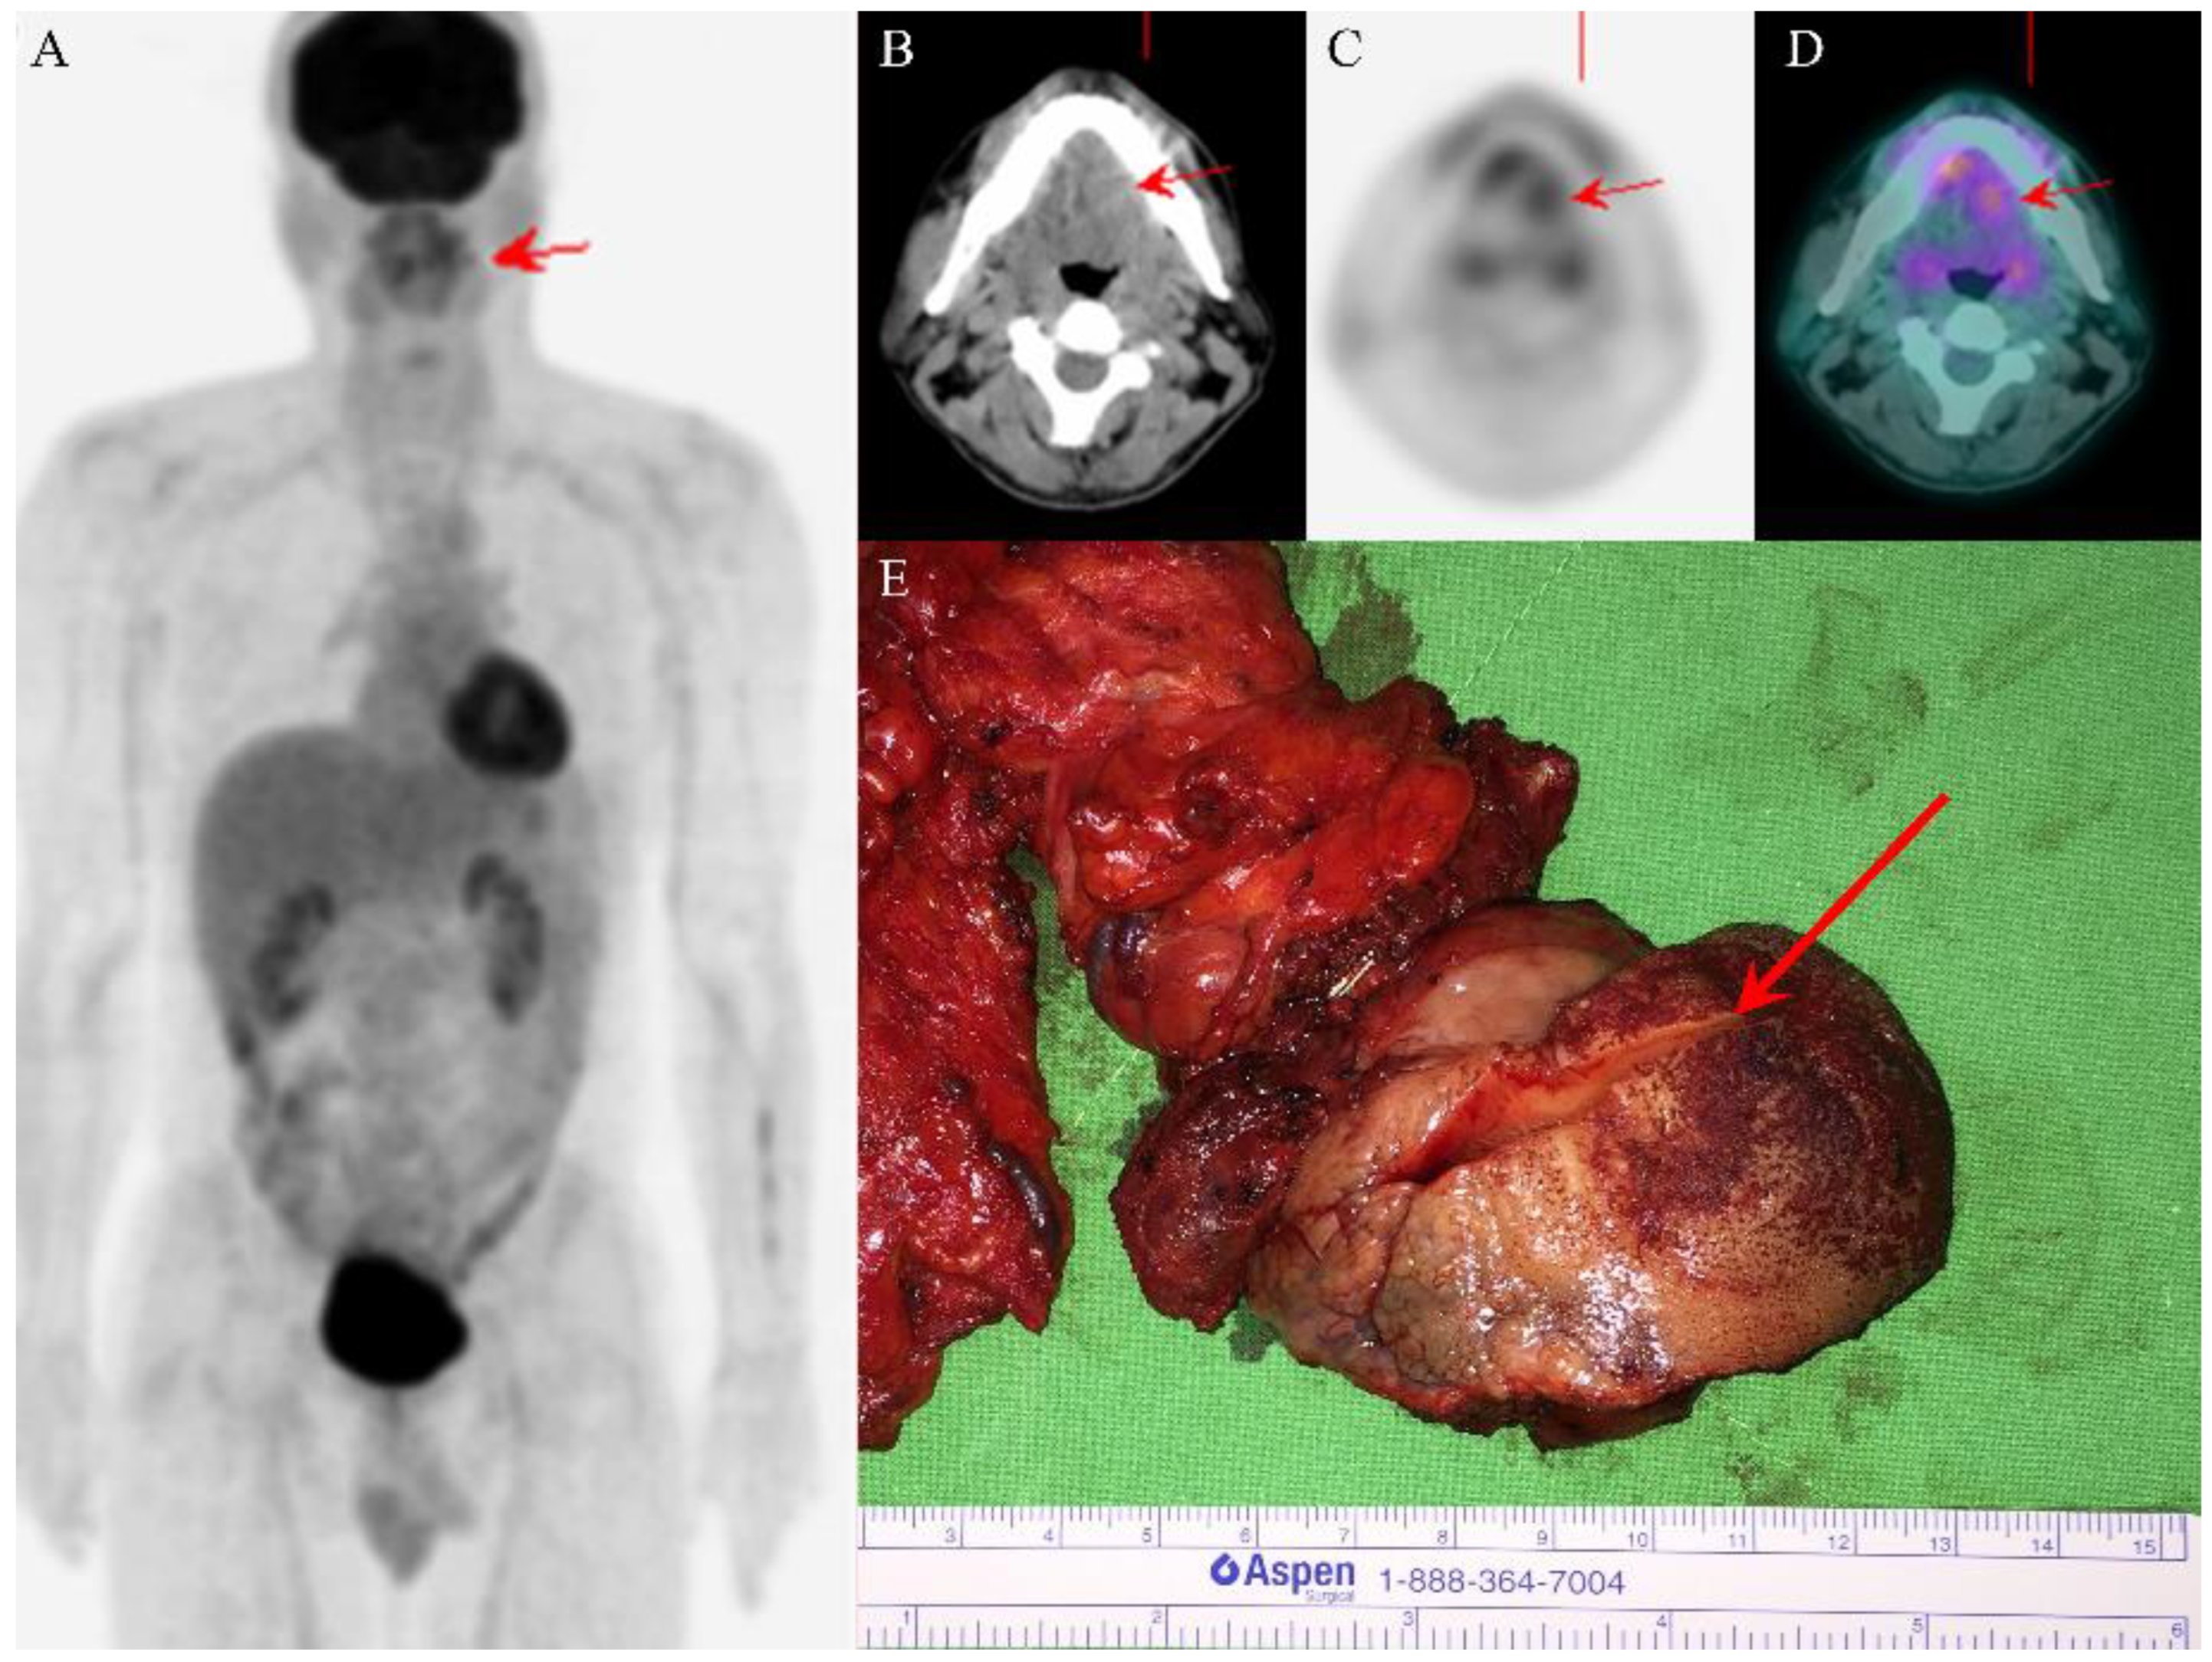

A nonsmoking man, aged 48 years, who did not chew betel nut, had a history of right tongue squamous cell carcinoma (SCC) and had received partial glossectomy 9 years previously at a medical center (Hospital A). He presented to Hospital A with dysarthria that had persisted for 6 months. A physical examination and initial head and neck computed tomography (CT) scan indicated no obvious tumor-like mass. Because the man’s symptoms persisted, head and neck magnetic resonance imaging (MRI) was arranged 4 months later and revealed a left tongue tumor. A biopsy of the tongue tumor was performed, and the pathology report revealed adenocarcinoma, intermediate-grade. Therefore, the patient visited our hospital for further survey. A physical examination revealed a 4 × 4 cm2 left ventral tongue tumor. The 18F-FDG positron emission tomography (PET)/CT revealed a hypermetabolic process in the tongue, consistent with recurrent tongue cancer without the involvement of regional lymph nodes or distant metastases (Figure 1A–D). The patient subsequently underwent wide excision of the left tongue tumor with bilateral selective neck dissection.

In the gross examination, an infiltrative ulcerated tumor was identified at the left lateral tongue border (Figure 1E); the tumor, measuring 5 × 4 cm2, crossed the midline and involved the ipsilateral tongue base and part of the extrinsic tongue musculature. Multiple small lymph nodes were noted at the bilateral neck and measured up to 0.9 × 0.8 cm2. Microscopically, the tumor exhibited diffusely infiltrating cords, tubules, and strands of epithelial cells with biphasic components of ductal and myoepithelial cells (Figure 2A,B). Perineural invasion and wide infiltration into adjacent skeletal muscle were observed (Figure 2C,D). In immunohistochemistry, CK7 and p40 highlighted a dual cell population of luminal and abluminal cells (Figure 2D,E). The neoplastic cells were negative for CD117, and the proliferation index, as determined by Ki-67, was low (<5%). No dysplasia was noted in the overlying mucosa. The surgical margin at the base of the tongue had tumor involvement. All dissected lymph nodes were negative for malignancy. In terms of histomorphologic findings and location, the tumor most closely resembled the SMA of the tongue. After discussing with the radiation oncologist for postoperative radiotherapy, the patient declined the radiotherapy for fear of side effects but received complete adjuvant chemotherapy due to margin positivity. Follow-up head and neck magnetic resonance imaging revealed no evidence of recurrence 23 months after surgery. The patient is in good health 2 years and 6 months after surgery and adjuvant chemotherapy.

Figure 1. PET/CT images revealed one ill-defined infiltrative tumor (red arrows) over the left tongue with high uptake of fluorodeoxyglucose and absence of regional lymph node involvement or distant metastasis (AD). The wide excision of the left tongue tumor grossly showed ulcerative mucosa and one ill-defined white submucosal tumor after cutting (red arrow) (E).